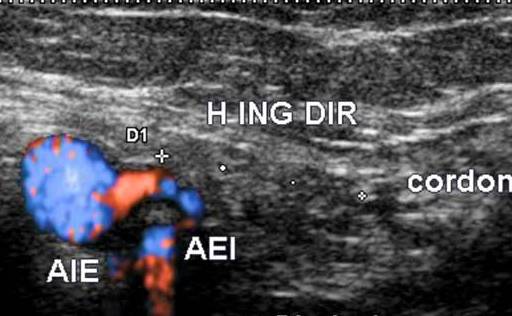

Herniile inghinale directe se exterioreaza prin foseta inghinala mijlocie inauntrul vaselor epigastrice. Coletul herniar este deci in pozitie postero-mediala in raport cu ostiumul arterei epigastrice inferioare.

Hernie directa

Eco doppler - Hernie inghinala directa. Coletul este postero medial

fata de ostiumul AEI